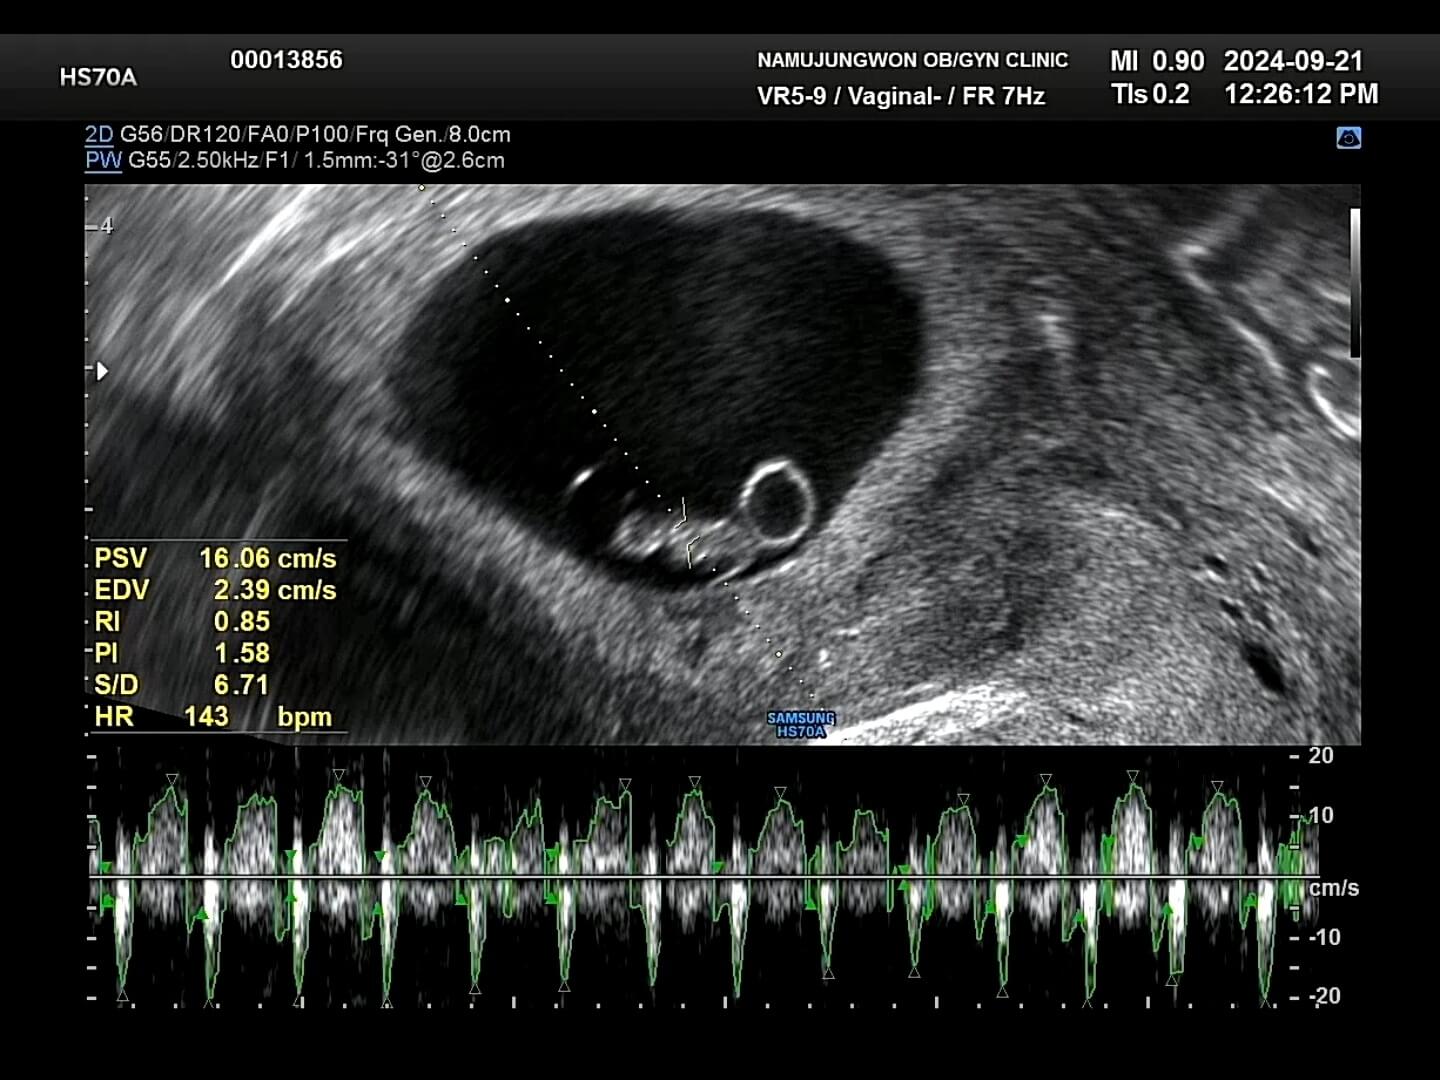

7주-심장박동 7주차 우리 꾸미는 심장박동 143bpm으로 정상범위로 아주 잘 자라고 있었어요. 임신 초기에는 워낙 불안정한 시기이기 때문에 뱃속에 아기가 잘 있는지를 보통 '임신 증상'으로 확인을 하곤 했습니다. 컨디션이 너무 안좋아서 '아, 우리 꾸미가 뱃속에 잘 있구나!' 라고 생각했어요.